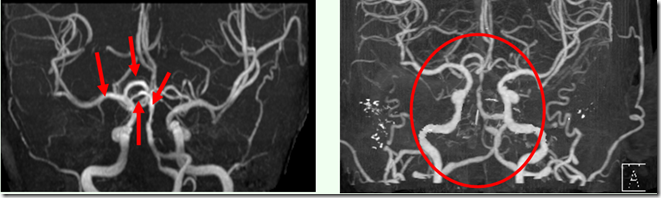

2013.01.10(四)按推后隔天,医院安排断层扫描。断层扫描显示,该部位之栓塞竟已完全消失

2013.01.07(一) 2013.01.10(四)

按推原始点前, 栓塞处清晰可见。 按推原始点后,栓塞处已消失。